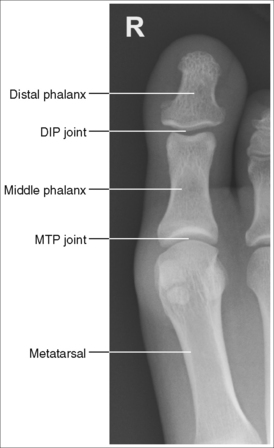

See Figures 6-1, 6-2, and 6-3 and Box 6-2.

FIGURE 6-1 First AP axial toe projection with accurate positioning. DIP, Distal interphalangeal; MTP, metatarsophalangeal.

The digit demonstrates no rotation. Soft tissue width and midshaft concavity are equal on both sides of the phalanges.